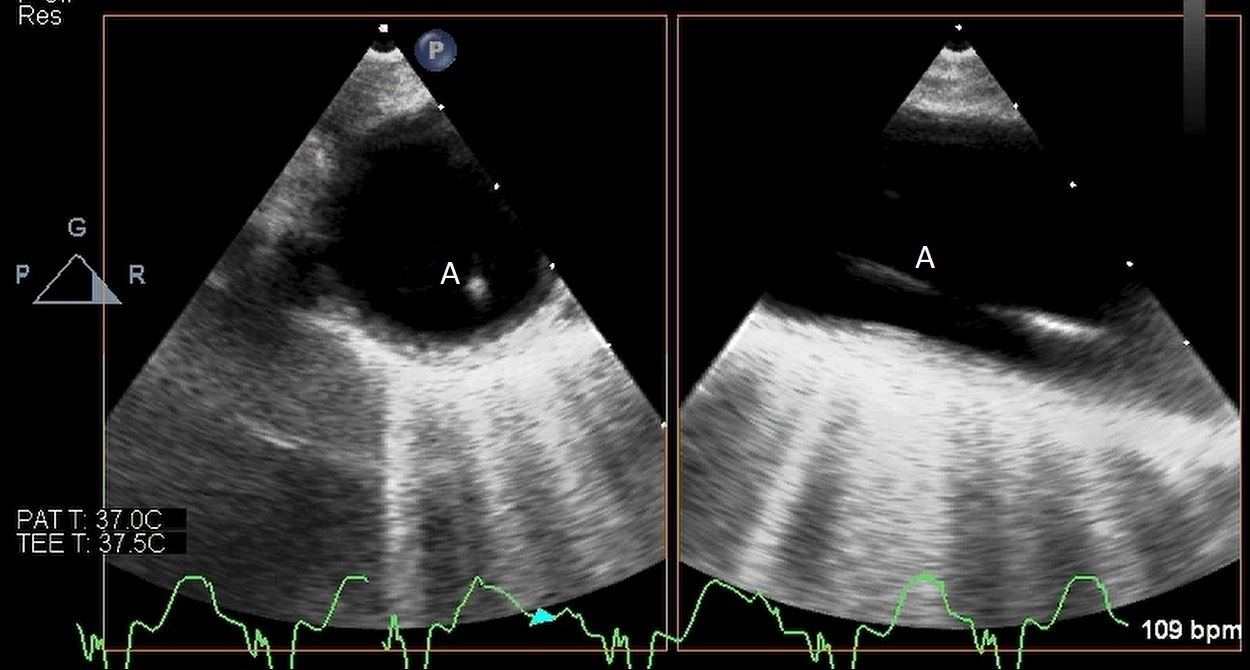

Impella (A) in the LV cavity caused disruption and damage to subvalvular apparatus resulting in flail segment (B) of the mitral valve.

Fig. 4.Impella (A) placement causing disruption and damage to subvalvular apparatus resulting in mitral valve flail (B) and mitral regurgitation (C).